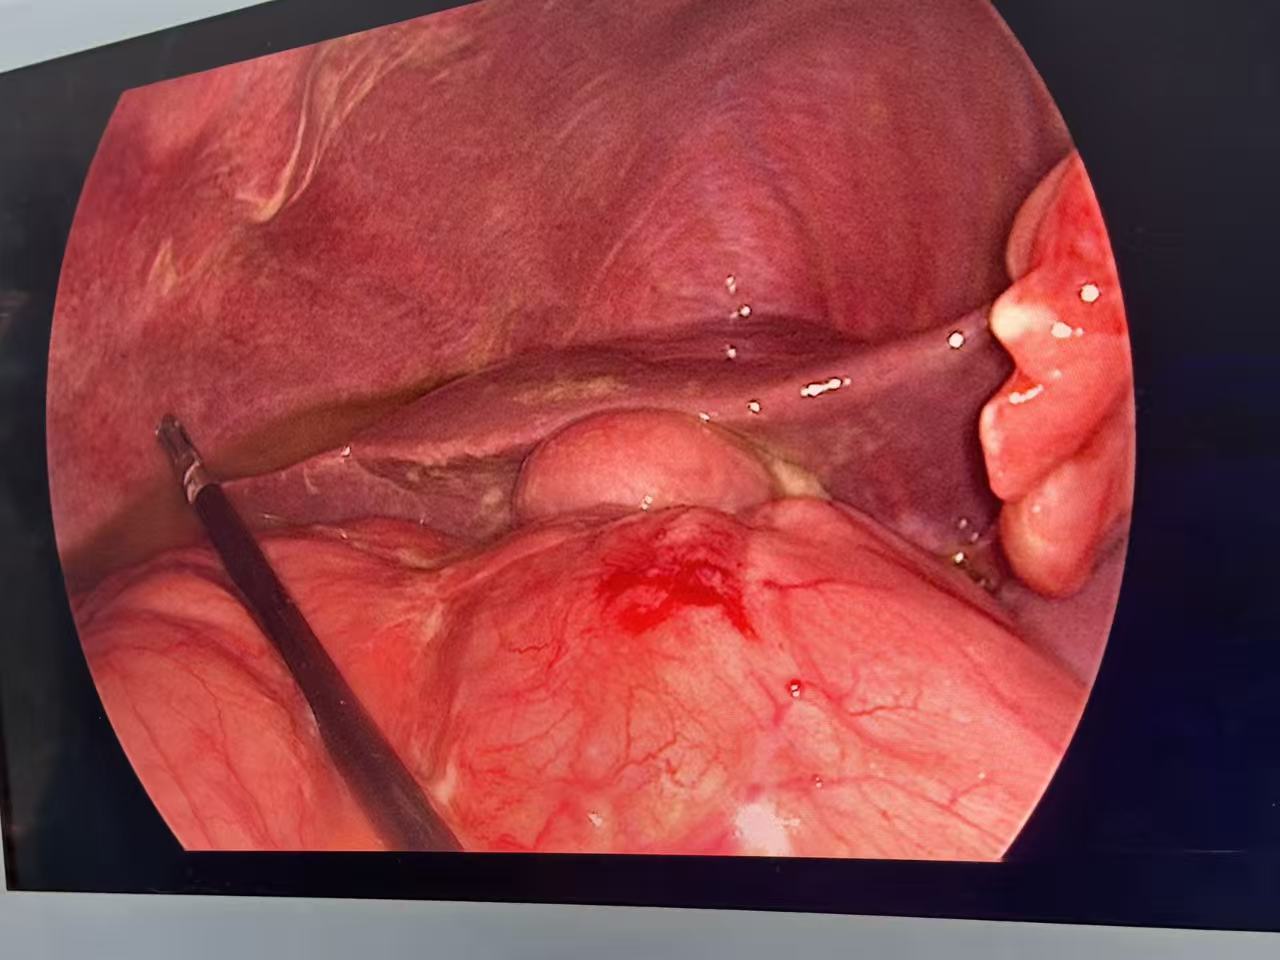

在医疗技术欠发达的年代,治疗穿孔的唯一方法是开腹大手术。而现在,腹腔镜微创手术已然成为治疗消化道穿孔的首选方案。近日,普外科成功为一名消化道穿孔患者实施了腹腔镜修补术,手术仅通过几个0.5-1cm的小孔就完成了穿孔部位的缝合与腹腔清理,患者术后第二天即可下床活动,大大缩短了住院时间。这种手术方式不仅创伤小、恢复快,还能更清晰地探查腹腔内情况,降低遗漏病灶的风险,为患者带来了更优质的治疗体验。

术中探查情况

术中处理穿孔位置